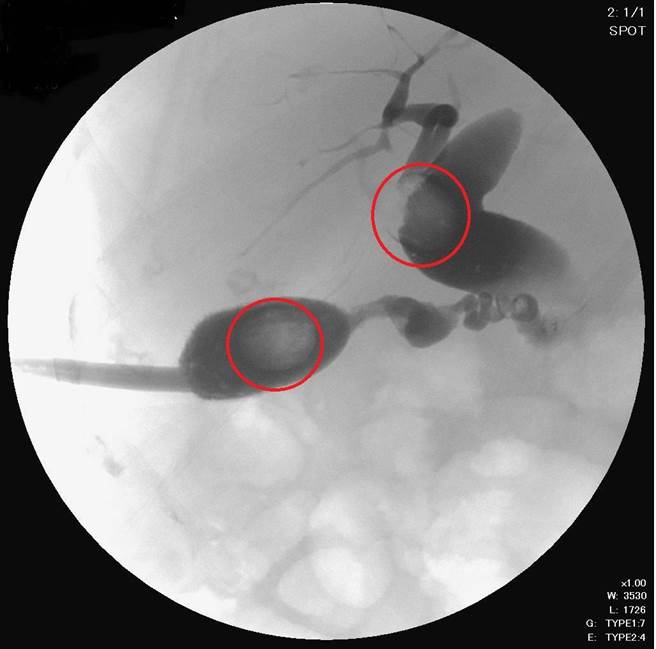

经过医师与病人及家属讨论后,阿嬷先接受放射科医师蒋咸嘉以经皮穿肝胆道引流,缓解发炎情形,然后施行经皮穿肝体外取石术移除结石。

经皮穿肝体外取石术,则是藉由放射线透视及超音波的引导辅助,使用针导管经皮穿肝进入胆管,扩张形成人工胆道廔管,再使用取石网将结石移除。